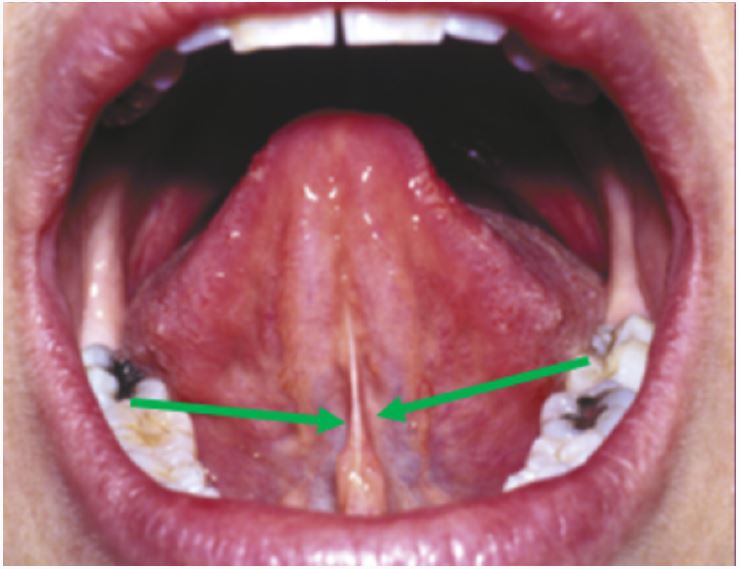

A patient with dental caries in a lower molar tooth is administered local anesthesia. To which area of the oral cavity is the anesthetic solution administered?

Near a major nerveAssist 5